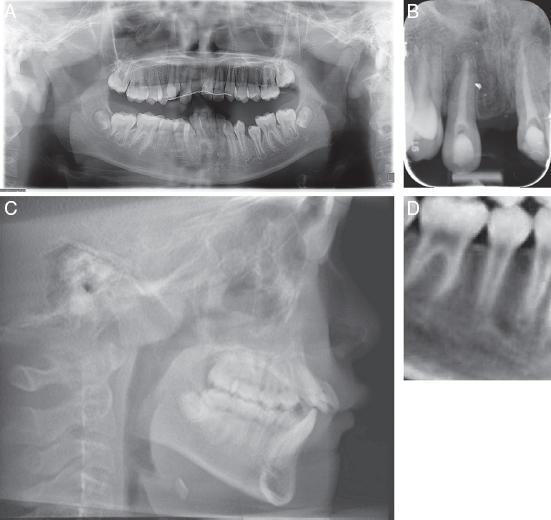

As a result of the trauma, the upper right central incisor (#11) was missing. The upper left central incisor (#21) and upper right lateral incisor (#12) were root canal treated and showed clinical and radiographic signs of ankylosis and replacement resorption (Figure 2A-D).

(A) Pretreatment dental panoramic radiograph. (B) Periapical radiograph showing resorption on the apical surfaces of #12 and #21. (C) Lateral cephalogram. (D) CBCT section showing developing tooth #45 with ¾ root length.